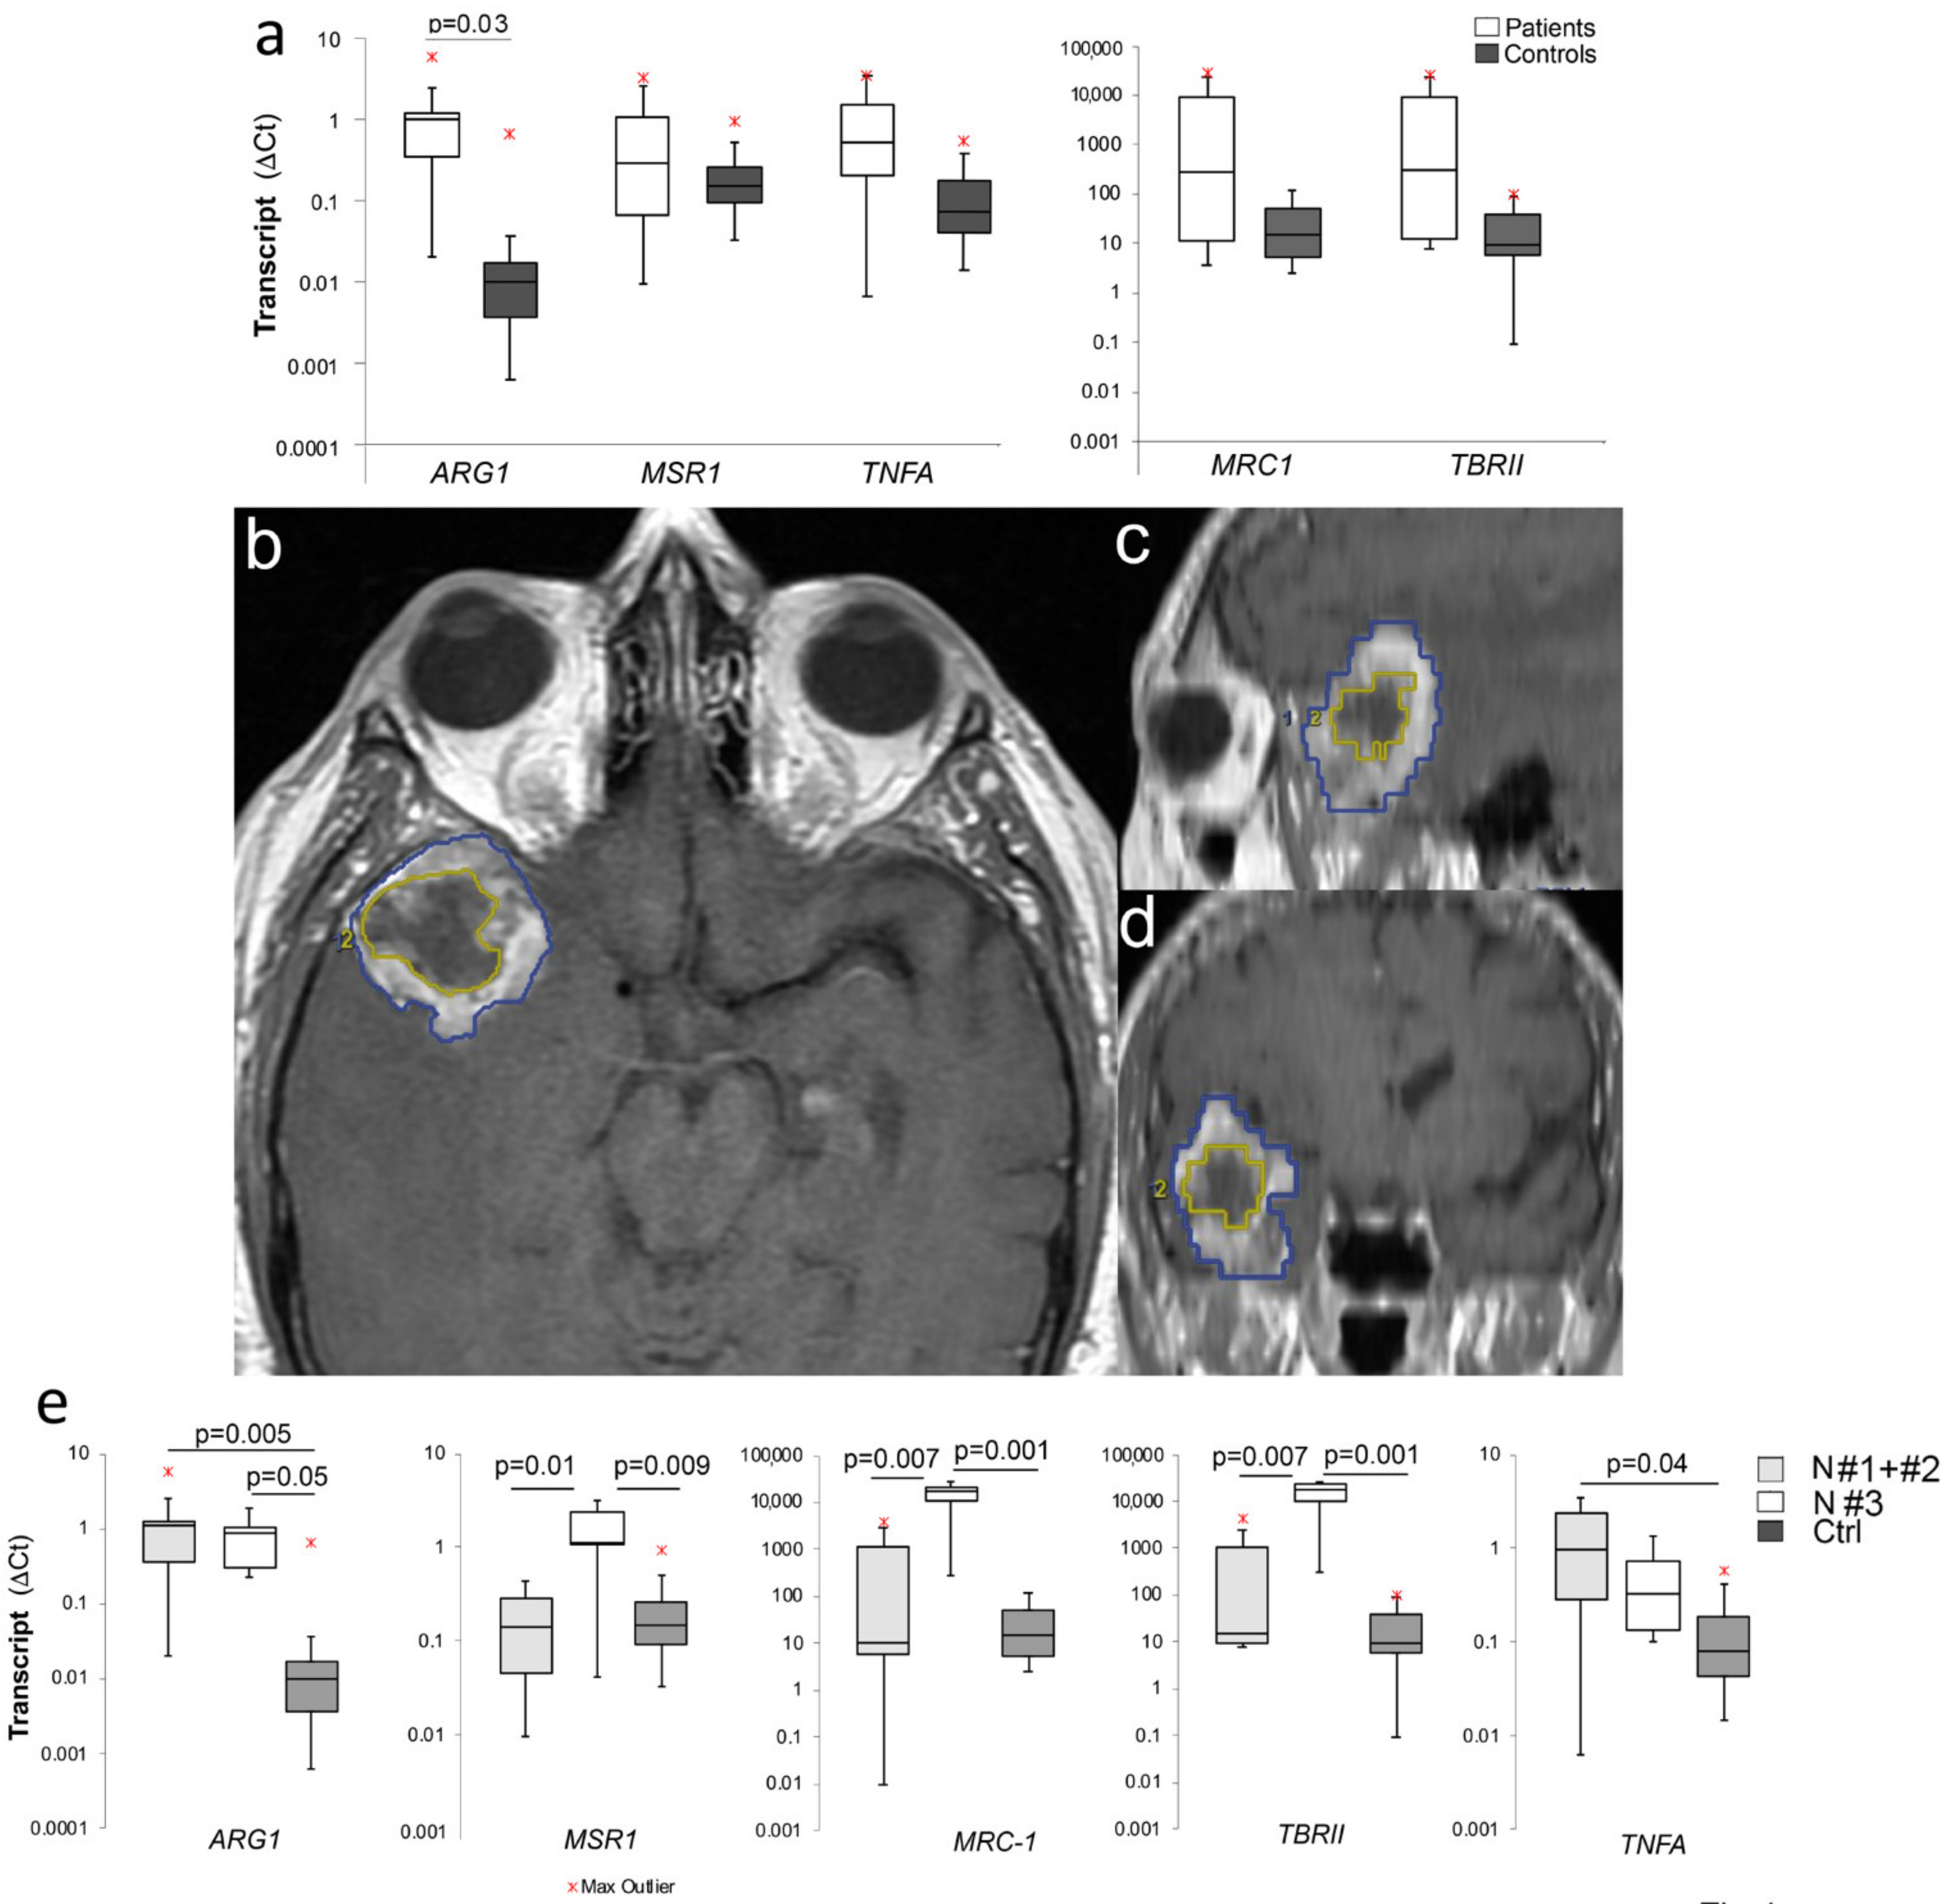

2.1. Increased M2 Gene Expression in PBMCs of GBM Patients